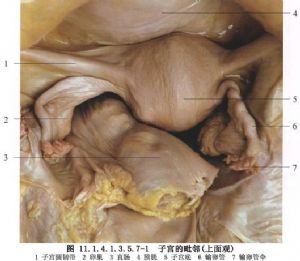

半腹膜外子宮切除手術用於子宮肌瘤的手術治療。